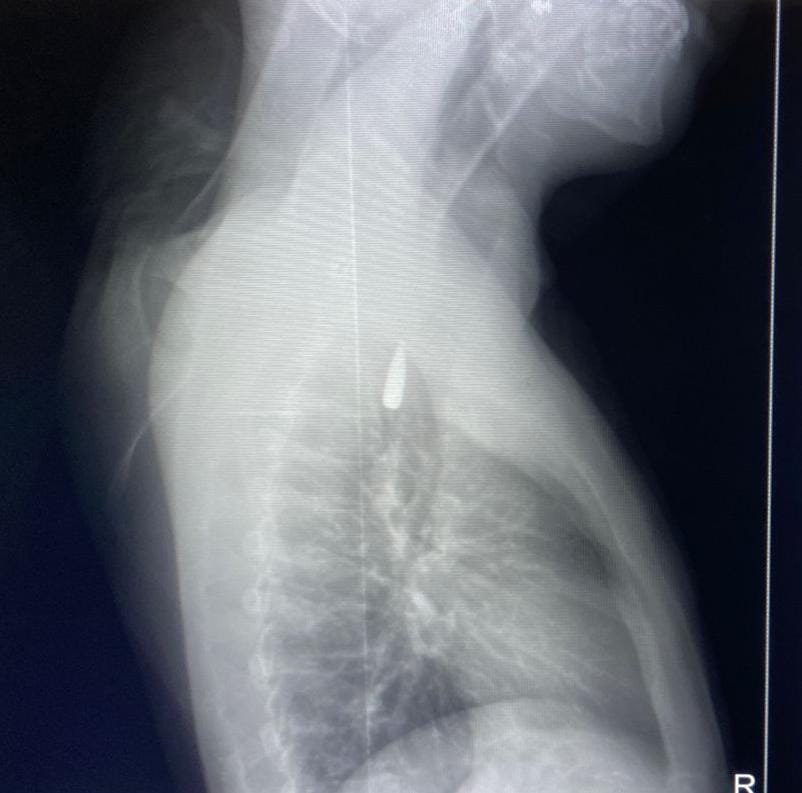

وأوضح الدكتور تامر عبد الله، عميد كلية الطب ورئيس مجلس إدارة المستشفيات الجامعية، أنه في يوم 21 أكتوبر 2025، تمكن فريق من أطباء قسم جراحة القلب والصدر والتخدير والمعاونين من إجراء جراحة دقيقة بالغة الخطورة لأحد المرضى المحجوزين من قطاع غزة، والذي كان قد تعرض لإصابة بطلق ناري في الرأس منذ فترة، استقر المقذوف على إثرها داخل تجويف القفص الصدري قرب الشريان الأورطي، وهو أكبر وأهم شرايين الجسم والمسؤول عن تغذية جميع الأعضاء الحيوية، وأضاف أن الفريق الطبي، رغم دقة الحالة وتعقيدها، نجح في استخراج المقذوف بأمان بعد عملية جراحية نادرة استمرت عدة ساعات داخل المستشفى الجامعي الجديد، حيث خضع المريض بعدها للرعاية الطبية اللازمة، وحالته حاليًا مستقرة وتحت المتابعة الدقيقة من الفريق المختص.